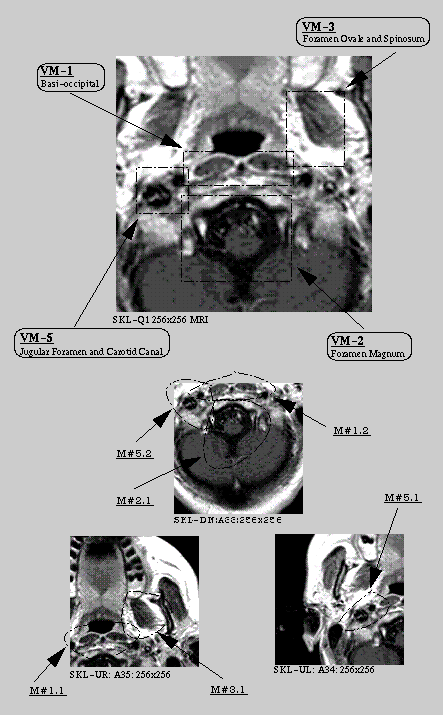

The rectangular windows specify the focus, and the ovals in the bottom images specify the corresponding matching images those were retrieved by the IMED system.